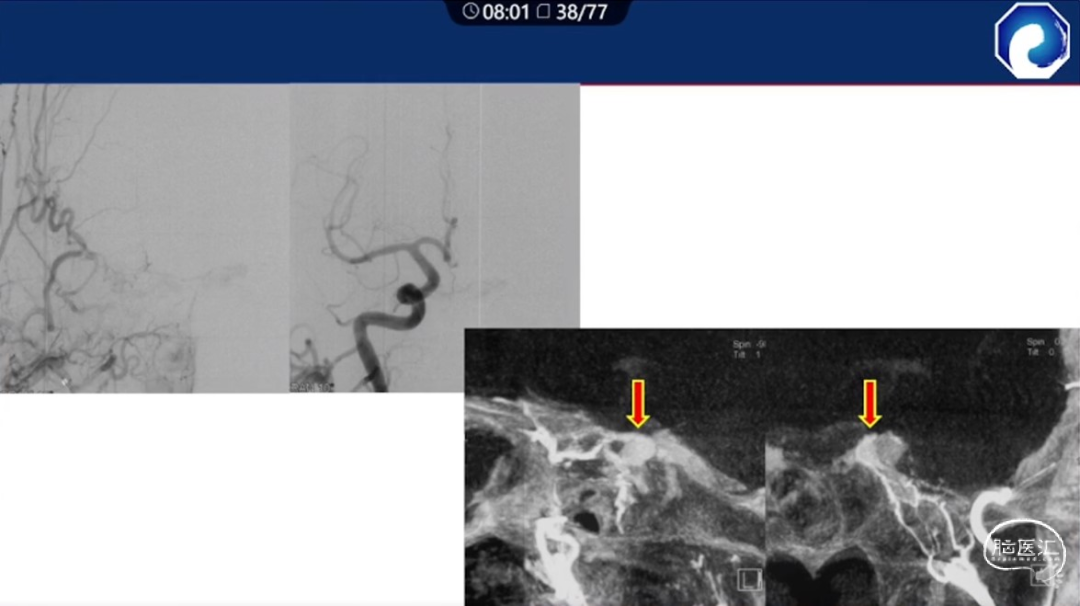

痿口静脉端的识别至关重要。

痿口静脉端精准完全闭塞是DAVF治愈的关键。

靶向性栓塞可以减少海绵窦分隔的过渡栓塞,有利于减少颅神经并发症,恢复海绵窦的正常引流功能。

减少栓塞材料应用。

减少与颈内动脉重叠,避免栓塞材料意外栓塞。